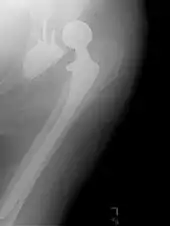

Hemiarthroplasty

Hemiarthroplasty is a surgical procedure that replaces one half of the joint with an artificial surface and leaves the other part unchanged. This class of procedure is most commonly performed on the hip after an intracapsular fracture of the femur neck (hip fracture). The procedure is performed by removing the head of the femur and replacing it with a metal or composite prosthesis. The most commonly used prosthesis designs are the Austin Moore and Thompson prostheses. A composite of metal and HDPE that forms two interphases (bipolar prosthesis) can be used. The monopolar prosthesis has not been shown to offer any advantage over bipolar designs. The procedure is recommended only for elderly/frail patients, due to their lower life expectancy and activity level. This is because over time the prosthesis tends to loosen or to erode the acetabulum.[84] Independently mobile older adults with hip fractures may benefit from a total hip replacement instead of hemiarthroplasty.[85]

Hip prosthesis for hemiarthroplasty. This example is bipolar, meaning that the head has two separate articulations.

X-ray of the hips, with a right-sided hemiarthroplasty